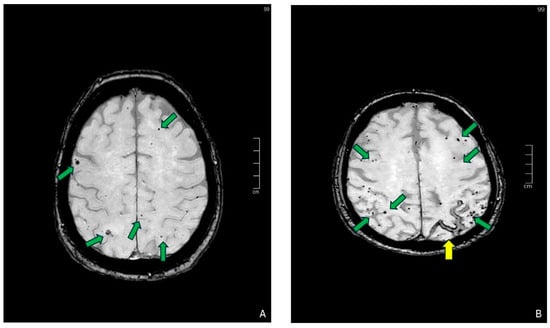

SWI is an advanced MRI technique that, like conventional T2*-GRE weighted imaging, is sensitive to substances that distort the local magnetic field (either paramagnetic or diamagnetic compounds). However, SWI, unlike T2*-GRE, can be considered the evolution of standard GRE sequences since that combines high spatial resolution (being a three-dimensional sequence) with specific post-processing techniques such as phase filtering and masking to highlight these substances. In SWI images, like in T2*-GRE images, calcifications and hemosiderin deposits appear both as small, round foci of hypointensity. For this reason, a critical technical aspect of SWI is the “handedness” of the MRI system, which influences the interpretation of phase shifts in the image, thus allowing the differentiation between paramagnetic (e.g., hemosiderin or deoxygenated blood) or diamagnetic substances (e.g., calcium). In fact, as already said, the accuracy in detecting the nature (i.e., calcium oh hemosiderin) of a SWI-hypointense focus might be challenging without looking at phase images. Depending on their positive and negative phase shifts, we can distinguish right- and left-handed systems in which paramagnetic and diamagnetic substances’ appearance changes. Indeed, it was described that right-handed systems, in which microbleeds appear hypointense and calcification hyperintense on phase images, seem the most effective in enhancing their differentiation [25] (Figure 4). However, the choice of the handedness of an MRI system depends on the vendor. Clinicians and radiologists should always be aware of the handedness of their system, even though there are some ‘tips’ to assess it when it is not explicitly specified [25].

Figure 4. Comparison between the Minimum Intensity Projection (mIP) of susceptibility-weighted imaging, right-handed Phase Imaging, and non-contrast CT scan (same patient). Phase Imaging aids in the differential diagnosis between diamagnetic substances (e.g., calcium, orange arrow in (A,B)) and paramagnetic substances (e.g., CMB, orange arrowhead in (D,E)). The diagnosis is confirmed in a non-contrast CT scan, which clearly demonstrates the presence of a microcalcification in the brain parenchyma (arrow in (C)) and no findings in the site of the microhemorrhage (orange circle in (F)).